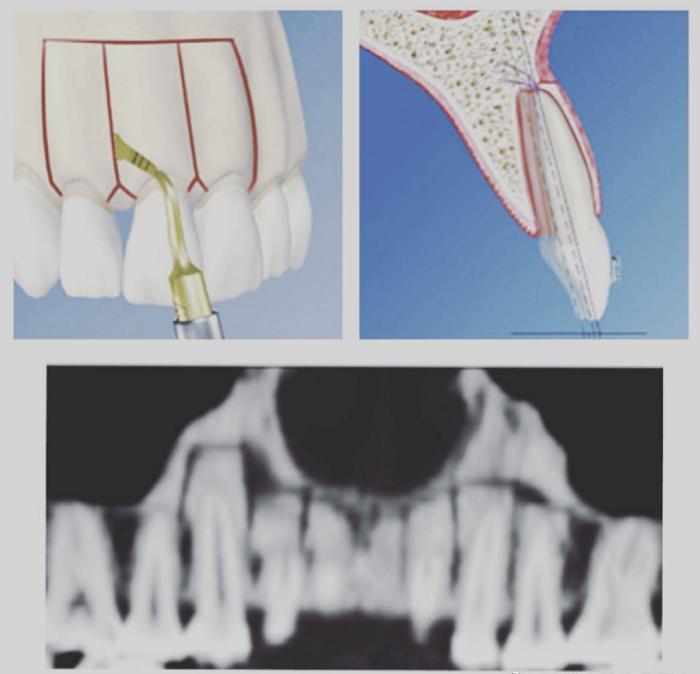

原理:松解骨皮质、去除骨阻力,但是骨松质是连接的,同时在骨皮质表面植骨,保持骨皮质健康,同时缩短疗程、提高速度。

由于成人患者骨骼没有生长潜力,只有骨改建能力,当牙齿需要较大范围移动时,骨皮质并不能跟随牙齿移动,不利于齿槽骨的健康,所以成人患者牙齿移动范围有很大局限性。为了提高正畸治疗效果,扩大正畸适应症,通过切开、断开牙根部的骨皮质(骨松质是连接的),当牙齿移动时,骨皮质与牙齿同时移动,减小了骨的阻力,牙齿移动的范围更大、速度更快。所以骨皮质切开术不但能解决中度骨性龅牙,还可以实现“快速正畸”。

为了使骨皮质切开效果更加完美,在骨皮质切开同时在表面植骨(盖氏Bio-Oss骨粉),可以更大范围、更快地移动牙齿,同时能够更好的保护牙槽骨健康,因为通过植骨,使骨皮质加厚加高,比术前更加坚固。